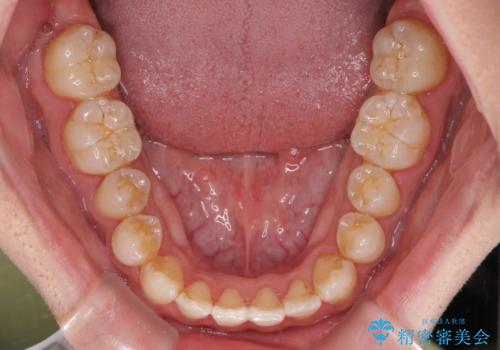

下顎前歯と上顎の部分矯正

- 上下の前歯の叢生を気にして来院された患者様です。

前歯のみの矯正治療を希望でしたが、上顎臼歯が舌側転位していたため、上顎は全体を、下顎は前歯のみを矯正治療することとしました。

矯正治療は上下全顎を行うことが大前提ですが、費用などの点から、今回は部分矯正を選択することとなりました。

患者様本人は咬みにくさを感じていないようですが、部分矯正は咬み合わせの改善が困難であることが多く、咬みにくさが残ることがあります。